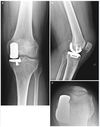

10

Q

CR TKA:

1. What is this prosthesis?

2. What is the design category and feature of this prosthesis?

3. What is the advantages of this type of prosthesis?

4. What is the disadvantages of this type of prosthesis?

A

1. Cruciate-retaining total knee arthroplasty.

2. Least constrained type of TKA, where ACL is removed, PCL is retained. On lateral view, can appreciate pegs instead of a box shape for the retained PCL, PE insert is also more flat to allow the femur to roll back onto the posterior part of bearing.

3. Advantages: i) Retaining PCL allows more bone conserving. ii) Keeping PCL helps to regulate flexion stability and keep flexion gap smaller. iii)Allows more consistent joint line restoration due to ii. iv) Allows more propioception feedback.iii) PCL tension influences femoral rollback, which is the progressive posterior change in femoral-tibial contact point as the knee moves into flexion.

4. Disadvantages: i) Harder to balance with severe deformities (avoid in varus >10 degs, valgus >15 degs). ii) Tight PCL in flexion will lead to increased PE wear. iii) Increase PE wear, increase particle debris, causing osteolysis, leading to dysruption of PCL from bony attachments, resulting in knee instability and repetitive subluxation. iv) Paradoxical forward sliding as knee flexes. PCL prevents posterior translation of the tibia relative to the femur but with ACL gone, tibia can still slide forward, causing sliding wear on PE insert.

11

CS TKA:

1. Posterior stabilised TKA.

2. Cruciate retaining TKA, has spine and cam mechanism in the posterior aspect of the knee, the cam is part of the femoral component between the two posterior femoral condyles, the PE insert has a post which the cam engages onto during flexion thus preventing anterior translation of the femur on the tibia (a function typically by PCL), no posterior roll back as like a normal knee as cam and post control rollback, PE inserts are more dished/congruent to the femoral condyle shape.

3. Advantages: i) Allows easier balancing in severe coronal deformities as ACL and PCL removed (balancing only required in one plane). ii)There is controlled flexion kinematics with spine and cam mechanism, so less sliding wear.

4. Disadvantages: i) Risk of dislocation due to femoral cam jump when flexion gap is too loose and with any varus/valgus stress applied when knee is flexed, thus allowing femoral cam to rotate in front of the post and rests in front of it. ii) Patella clunk syndrome due to scar tissue getting caught in the box. ii) Tibial post wear and breakage. iii) More bone is removed from middle of distal femur. iv) Flexion gap is bigger as PCL is removed, to in order to balance the extension gap additional distal femur is removed and so causing joint line elevation and subsequently patella baja